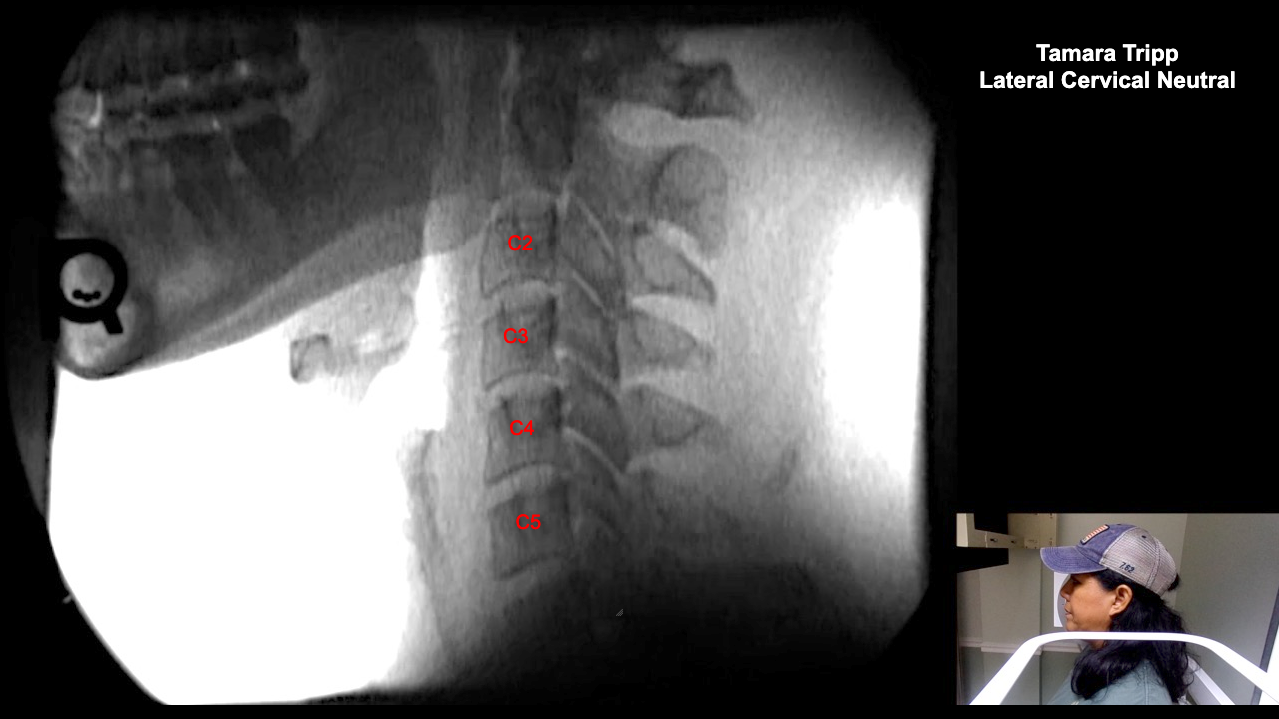

Home > Tamara Tripp 7-3-25